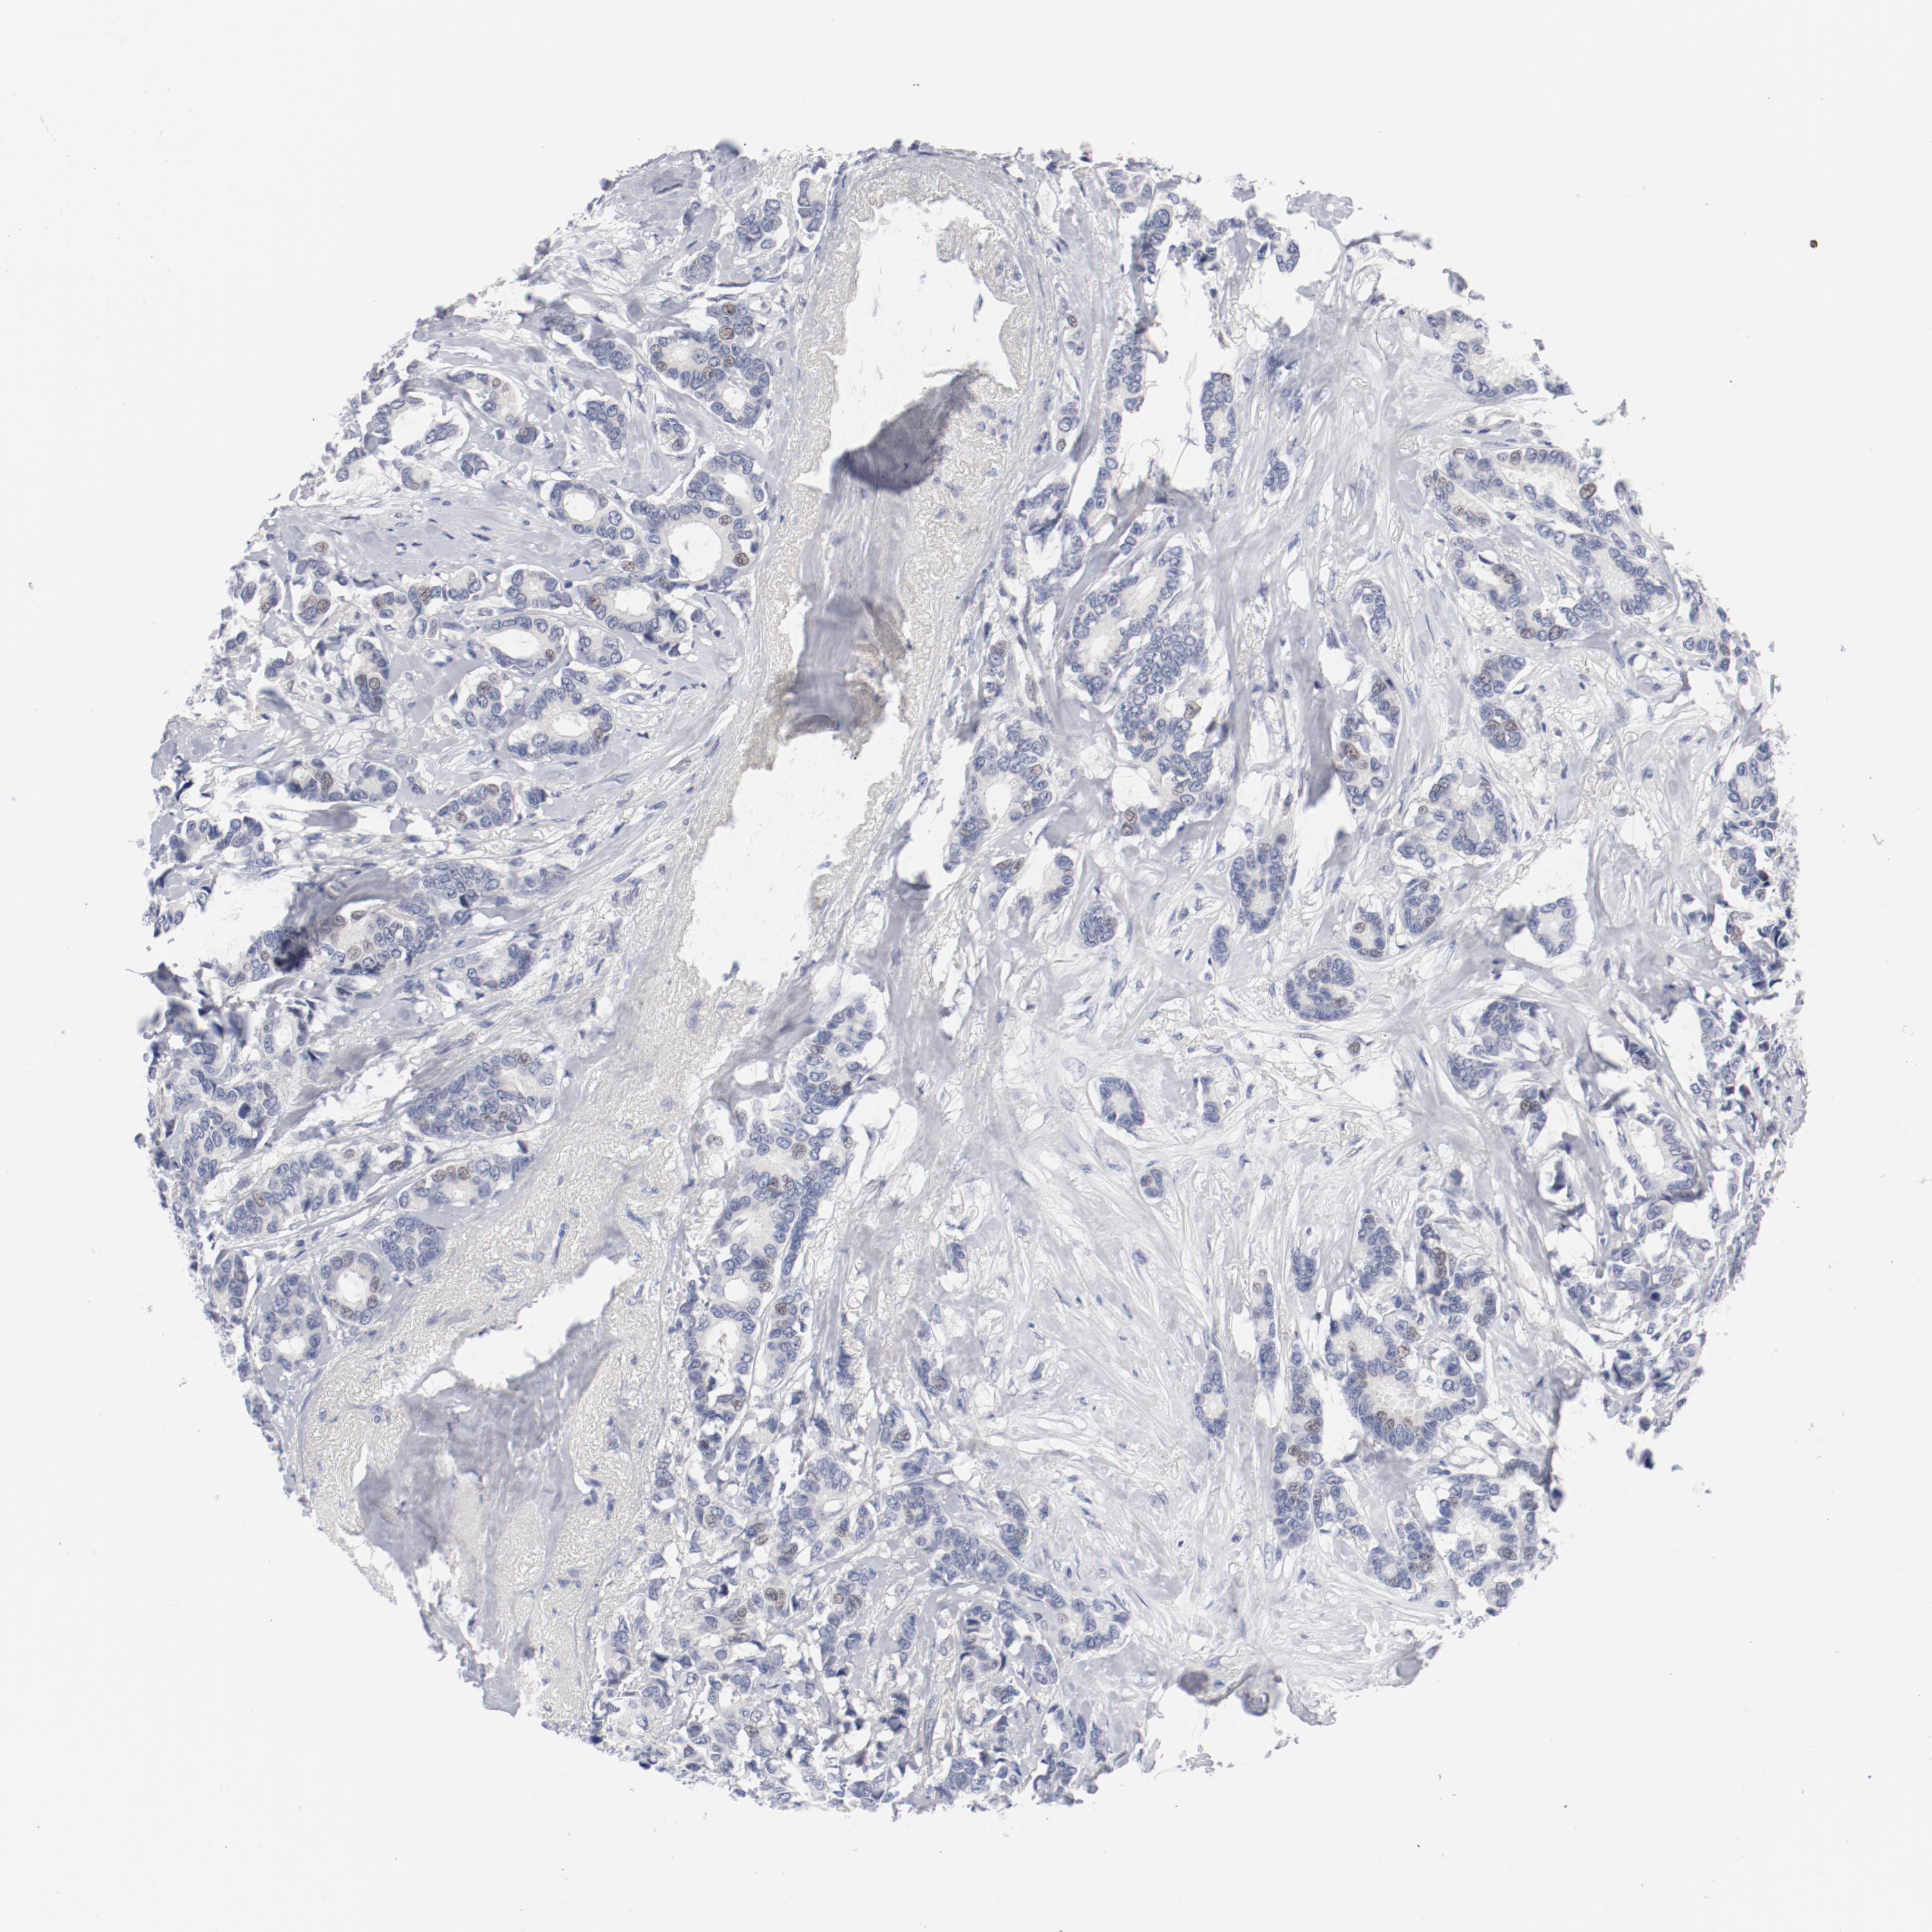

CANCER BREAST CANCER Show tissue menu

BRCA TCGA BRCA VALIDATION PROTEIN EXPRESSION